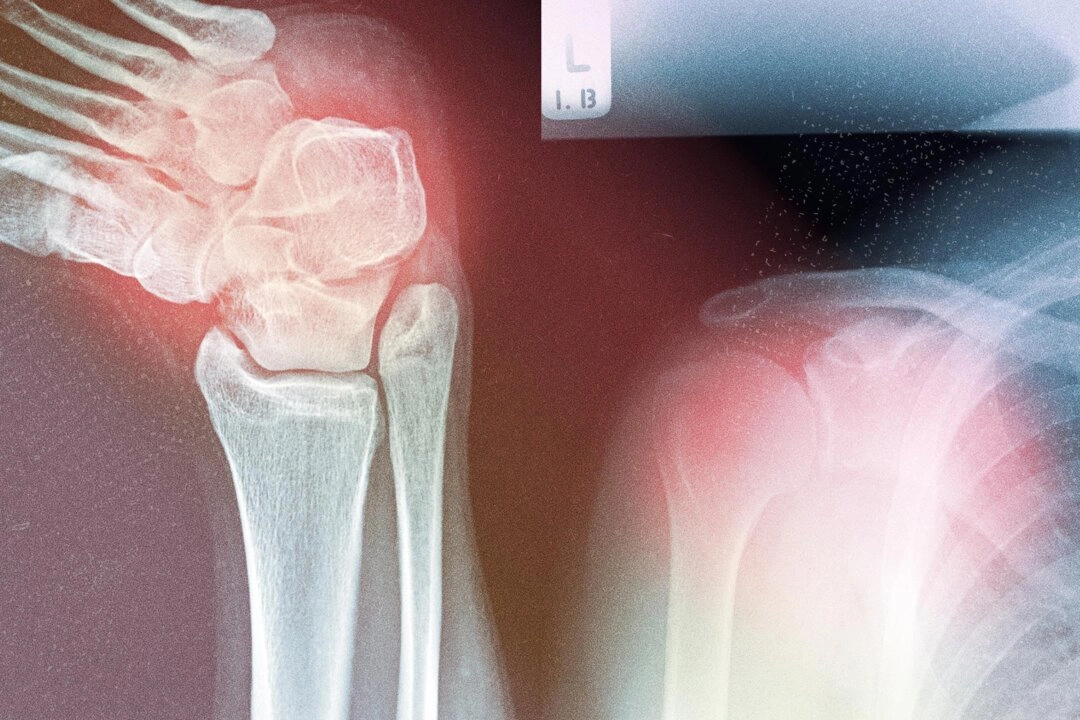

骨骼肌肉疾病:全球流行趨勢與數據

不幸的是,對於許多骨骼肌肉疾病(如骨關節炎、骨質疏鬆症、痛風、肌肉減少症和類風濕性關節炎),這種全局整體考慮的方法並不是主流。隨著人口老齡化,這些疾病的發病率迅速上升,目前在美國影響超過 1.21 億人。

在全球,慢性骨骼肌肉疾病已成為造成行動障礙甚至殘障的主要原因。它們不僅影響行動能力,還會降低生活質量,並增加跌倒、骨折和住院風險。

2021 年,全球約有 6.07 億人患有骨關節炎,較 1990 年增加了 137%。類風濕性關節炎和痛風的病例也分別激增 125% 和 150%。